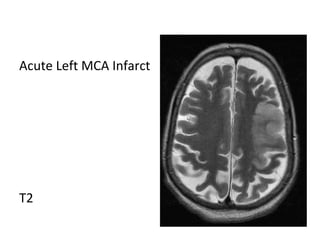

Acute Left MCA Infarct

T1

T2

DWI

ADC